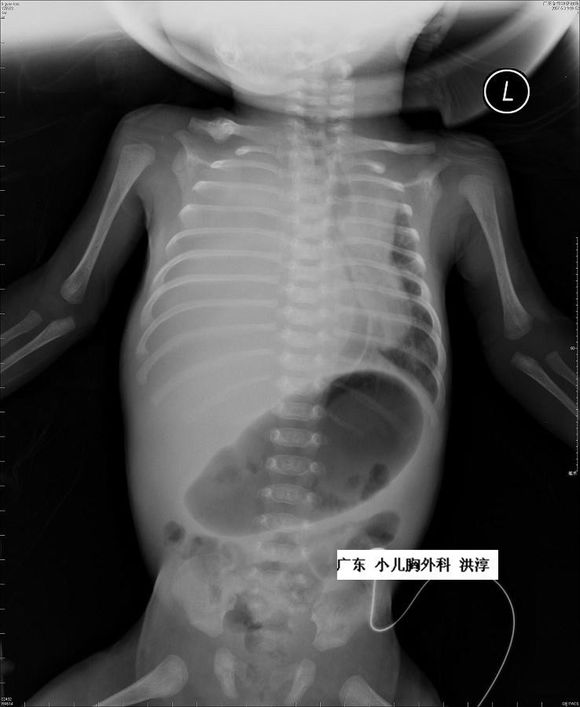

1. 持续性胎儿胸腔积液会使正在发育的肺受到压迫,肺内液体减少,使肺泡细胞数量及小支气管减少,严重者可导致肺发育不良。

2. 大量胸腔积液可使纵膈移位,压迫下腔静脉和心脏,引起胎儿心功能衰竭。诸多问题都需要有效的产前进行干预。胸腔积液合并羊水过多可能是由于大量胸腔积液压迫食道,影响胎儿吞咽羊水。因此对胎儿大量胸腔积液应进行干预措施,通过非侵入性或侵入性治疗来缓解胎儿症状、促进胎肺发育。

对于胎龄大于32周的胎儿胸腔积液,出生后在建立静脉通路,保证体循环血容量的情况下给予胸腔穿刺并密切观察可能是最好的选择。

对小于32周的FHT胎儿,有3种方式提供选择:胸腔穿刺术、胸腔羊膜腔分流,以及胸腔-母体皮下引流。但应该注意的是,这些操作均有可能出现感染、出血、胎膜早破、早产及损伤胎儿的风险。